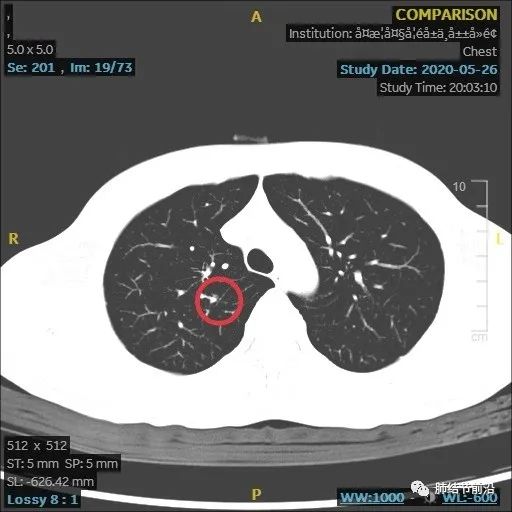

结节变大,形态变化,出现多中心微小结节堆积形态,而之前实性8mm结节却不见了。

虽然结节变大,但这个时候反而安心了,大的8mm实性结节消失,变成多中心微小结节。这样不符合肺癌的发展规律,考虑炎症性结节。因为恶性结节,只会实性成分扩大。